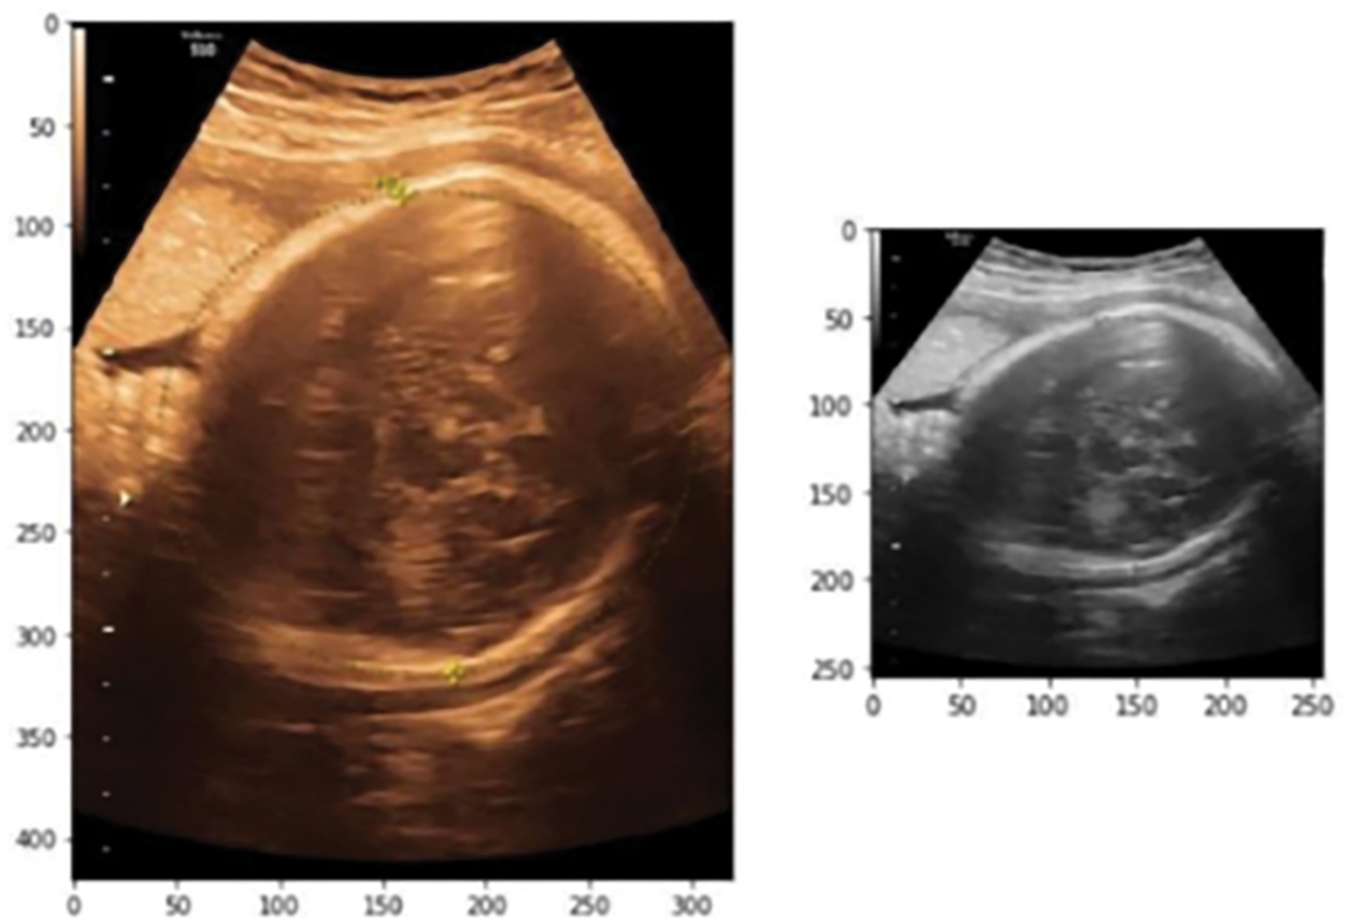

Inexperienced human observers may benefit from the assistance of an automated system in achieving an accurate measurement. In this work, our focus is on monitoring the HC, as it holds the potential for calculating the GA and tracking the fetus’s development. In addition, the embryonic head is more visible than the embryonic abdomen. Systems for automatic HC measurement have used the randomized Hough transform [4,5], Haar-like features [6–9], multilevel thresholding [10], circular shortest paths [11], boundary fragment models [12], semi-supervised on region graphs [13], active contouring [14,15], intensity-based features [16], and text on created features [4]. Fig. 1 displays the ultrasound fetal head images from the public HC18 dataset.

Figure 1: Ultrasound fetal head images from the public HC18 dataset